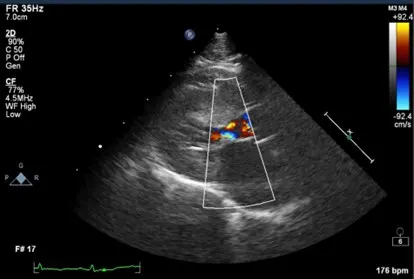

Diagnostics were triaged in order of importance because of the severity of disease and suspicion of a previous thromboembolic event, as well as to reduce patient stress. An echocardiogram to evaluate for underlying cardiac disease was determined to be top priority; results revealed concentric hypertrophy of the left ventricle (5.55 mm), papillary muscle hypertrophy, endomyocardial fibrosis, and end-systolic cavity obliteration. The left atrium was moderately dilated (left atrium:aorta, 2.3; 2D left atrial diameter [LAD], 22 mm; M-mode LAD, 23 mm) with presence of spontaneous echo contrast (ie, smoke). A moderately sized thrombus was observed in the left atrial appendage (Figure 1).

FIGURE 1 Left atrial thrombus in a cat with a history of hypertrophic cardiomyopathy presented for lameness. A slightly obliqued, right parasternal, 4-chamber-long axis view of the heart reveals a thrombus in the left atrium, which is moderately dilated.

Moderate systolic anterior motion of the anterior leaflet of the mitral valve apparatus was seen, as well as mild mitral valve regurgitation. Sinus tachycardia was present. The remainder of the study was unremarkable. No evidence of congestive heart failure (CHF; ie, no evidence of abnormal B-lines, pleural effusion, pericardial effusion) was found.